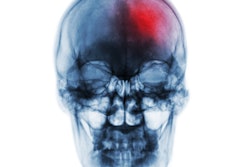

Artificial intelligence (AI) software developer Viz.ai has launched a new AI platform designed to help clinicians enhance their ability to triage and care for stroke patients.

The ultimate goal is to reduce the time it takes to diagnose and assess patients, begin endovascular intervention, and follow up with appropriate post-treatment care.